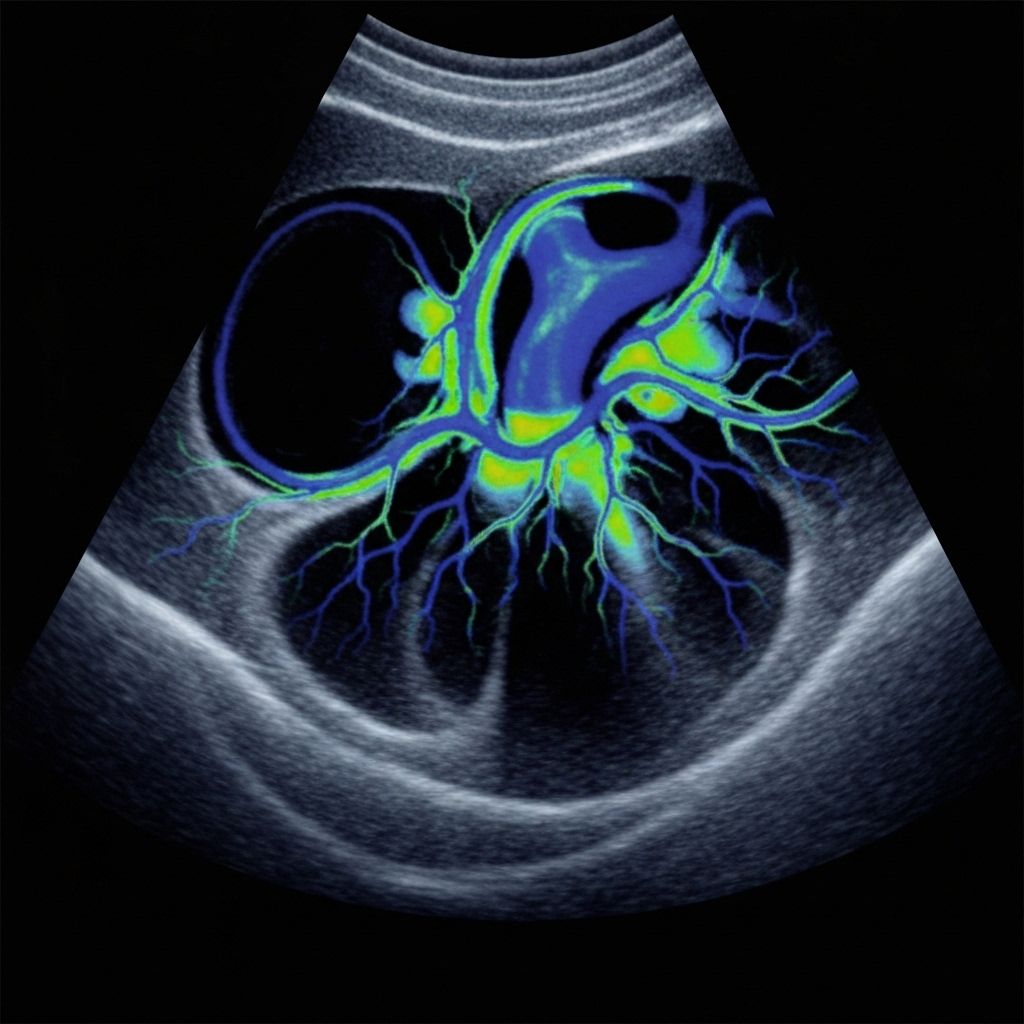

Detailed echocardiography for fetal and adult hearts. Non-invasive ultrasound assessment of structure and function to aid timely diagnosis.

High-resolution ultrasound for abdomen, obstetric, pelvic, and vascular studies. Colour Doppler evaluates blood flow and vessel patency.